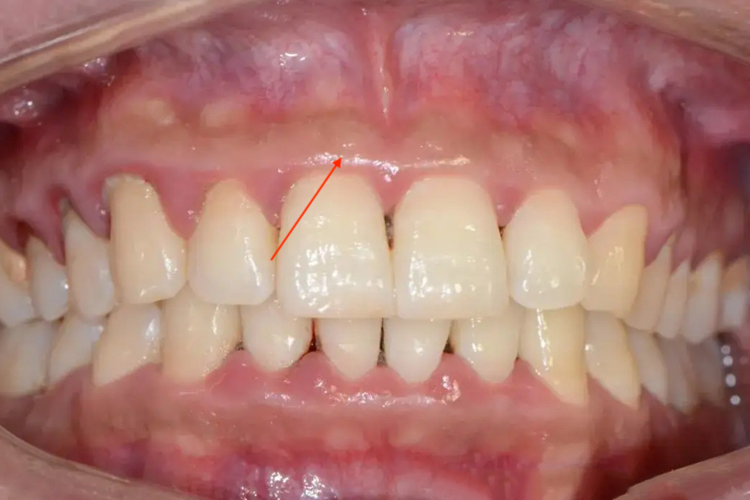

牙槽骨位于人体口腔中,是上下颌骨包围和支持牙根的部分,颌骨上与牙齿相连接的骨性突起部分。由固有牙槽骨和支持骨组成,牙根支撑,呈凹槽状。X线片可见一条阻射线沿着牙周膜间隙相对应的透射线。